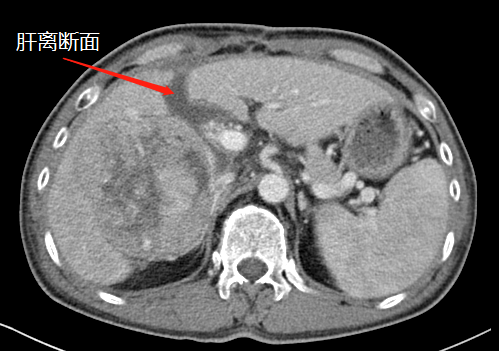

术前,左肝体积很小

第一次术后,结扎门静脉劈开肝脏

“9月底,在第一阶段手术中,我们先将患者的右侧门静脉结扎(肝的血液供应通过门静脉和肝动脉进行),保留肝动脉、肝静脉和胆管的完整性,然后沿肝中裂将肝脏的左右叶彻底劈开。”据胡伟介绍,人体肝脏具有很强的再生功能,结扎门静脉右支后左侧肝脏由于过量的血液供应短期内迅速增大;同时将患者的左右肝脏离断,降低了肿瘤侵犯左侧肝脏的可能。

经过20天左右的“养肝”,经CT复查显示,患者的左侧肝脏体积已增长至42.8%,这时候,也就达到了我们说的“养大好肝、再切病肝”,因为此时好肝已经足以维持患者身体的运转需要。